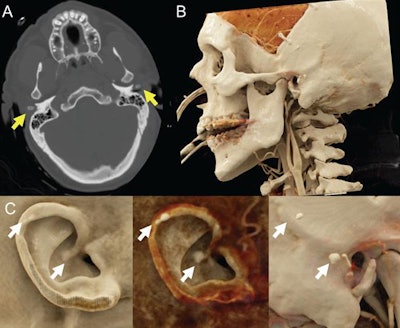

In a recent case study, Caton and Malone acquired the CT scans of a 47-year-old man with a history of traumatic brain injury who had previously undergone craniectomy to relieve pressure in the skull. They used advanced volume rendering software (syngo.via, Siemens Healthineers) to cinematically render the CT data and generate photorealistic images.

The resulting cinematically rendered images greatly improved depth perception as well as the visualization of surface textures and underlying calcification below the surface of the skin, compared with conventional CT, Caton told AuntMinnie.com. As a result, the researchers were able to spot calcification in both of the patient's ears, which physicians had not recognized on a prior physical exam.

Head CT scan of a 47-year-old man with a history of traumatic brain injury (A). Auricular calcification is evident on the patient's cinematically rendered CT scans (B, C). Image courtesy of Dr. Michael Caton.Manually adjusting the CT window and level settings also gave the researchers the opportunity to selectively emphasize or suppress tissues with different radiographic densities on the cinematically rendered images -- enabling them to alternate between views of the skin's surface and the underlying bony and soft-tissue structures.